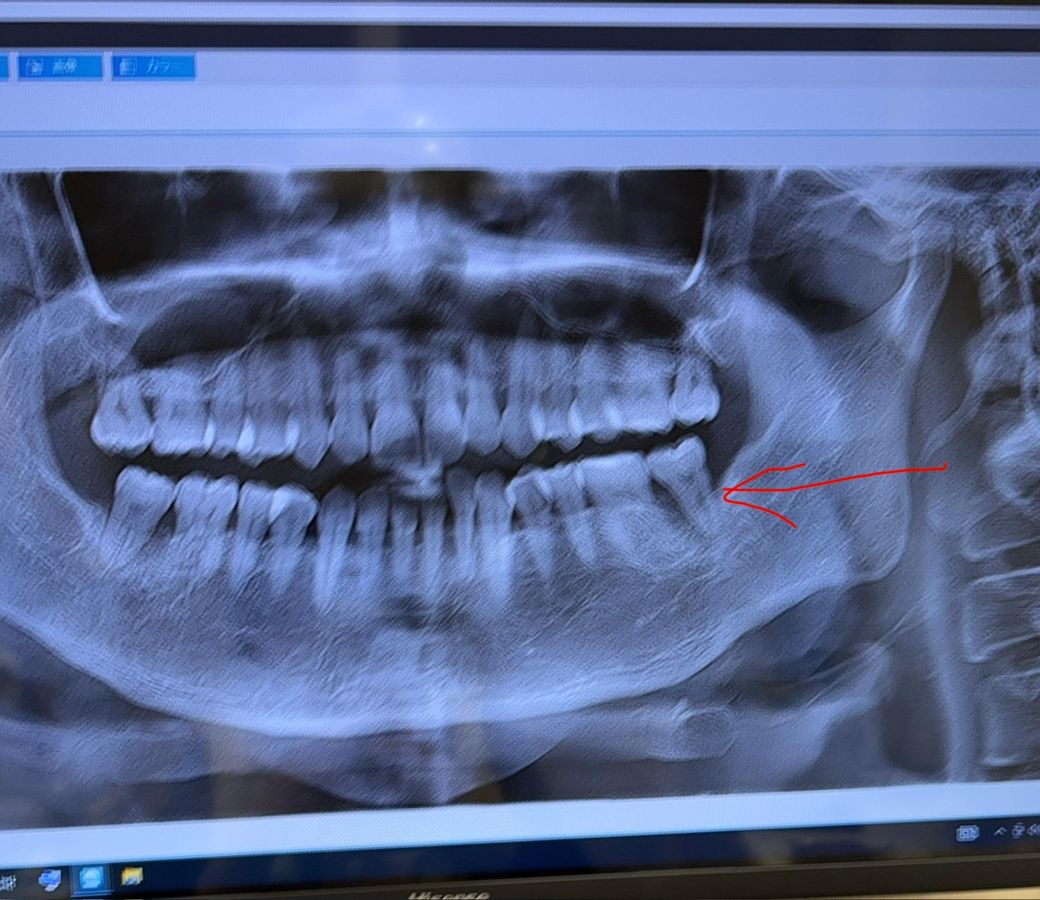

갑자기 이가 흔들리는데요 임플란트 해야할까요?

2주전 점심에 갑자기 왼쪽 아래 어금니가 엄청 아프더니 저녁 전에 만져보니 흔들리더라구요

병원 갔더니 치주염으로 뼈가 녹아있데요.

바늘같은걸로 찔러서 검사했는데 저쪽은 8이라고 하더라구요; (3이 기준)

엑스레이상으로도 뼈가 많이 녹았고, 그동안 증상은 없었어도 계속 염증이 잇몸뼈를 녹이고 있었던 겁니다.

프루빙 수치도 8이라면 뼈가 녹은게 확실하고요.

갑자기 해외에서 통증이 생겨 걱정이 많으시겠어요 불행하게도 죄송하지만 왼쪽 아래 맨 끝에 치아는 발치 해야 합니다 발치 하지 않고 버틸 시에 해당 부위 뼈는 더욱 사라져서 나중에 뼈이식을 많이 하셔야 임플란트 치료가 가능할 것입니다 임플란트 말고 다른 치료는 근본적인 치료가 아니라서 하셔도 계속 불편 하실 수 있습니다 빠르고 정확한 치료를 하려면 발치 후 임플란트 치료 하셔야 합니다 그리고 반대편인 오른쪽 아래 맨끝 치아도 상태가 좋아 보이지 않습니다 ㅜㅜ